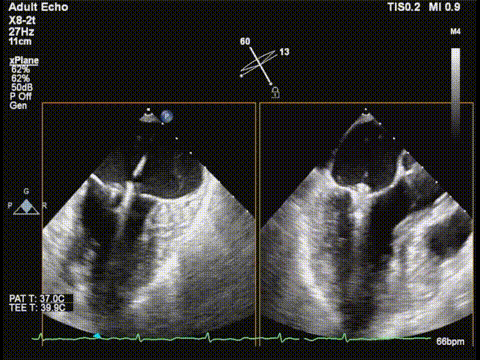

三尖瓣胃底界面

三尖瓣胃底界面color